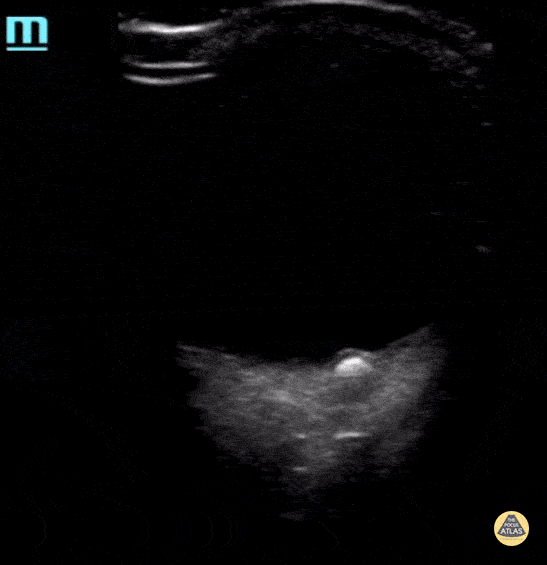

Note the hyperechogenic area that represent the drusen in the optic disc. Contributor: Maher M. Abulfaraj, MD, @mahermabulfaraj